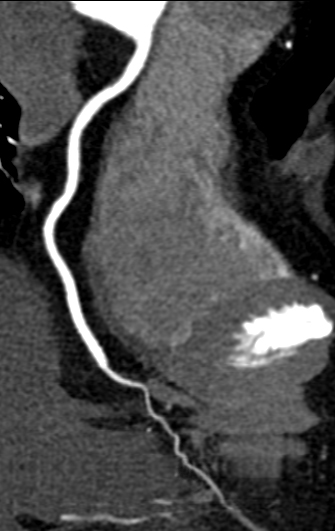

大范围低剂量CTA成像

采用业内最先进液态金属轴承技术的超大热容量球管,结合独有的低千伏、低毫安成像模式,天河640可实现冠脉、主动脉、下肢动脉等全身各部位大范围扫描、微辐射剂量的检查。低千伏扫描模式有效降低辐射剂量、对比剂总量、对比剂浓度、对比剂注射速率,降低肾功能不全受检者增强检查风险、减少对比剂外渗风险、并可大幅度提升增强检查碘对比剂对比度,提升强化效果;同时,系统还可根据不同患者体型和扫描协议自动推荐扫描管电压,在降低患者扫描剂量的同时,优化对比度噪声比。

图片说明:肺动脉+主动脉全程+下肢动脉大范围一次扫描成像。